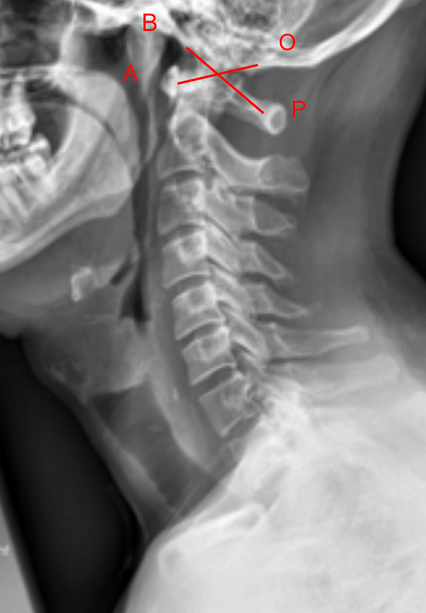

• Obtain a neutral lateral cervical spine X-ray (as shown in the provided image).

• Basion (B): The anterior margin of the foramen magnum.

• Opisthion (O): The posterior margin of the foramen magnum.

• Anterior arch of the atlas (A): The midpoint of its anterior cortex.

• Posterior arch of the atlas/spinolaminar line (P): The midpoint of its posterior cortex.

• Line 1 (BA): From the basion (B) to the midpoint of the anterior arch of C1 (A).

• Line 2 (OP): From the opisthion (O) to the midpoint of the posterior arch of C1 (P).